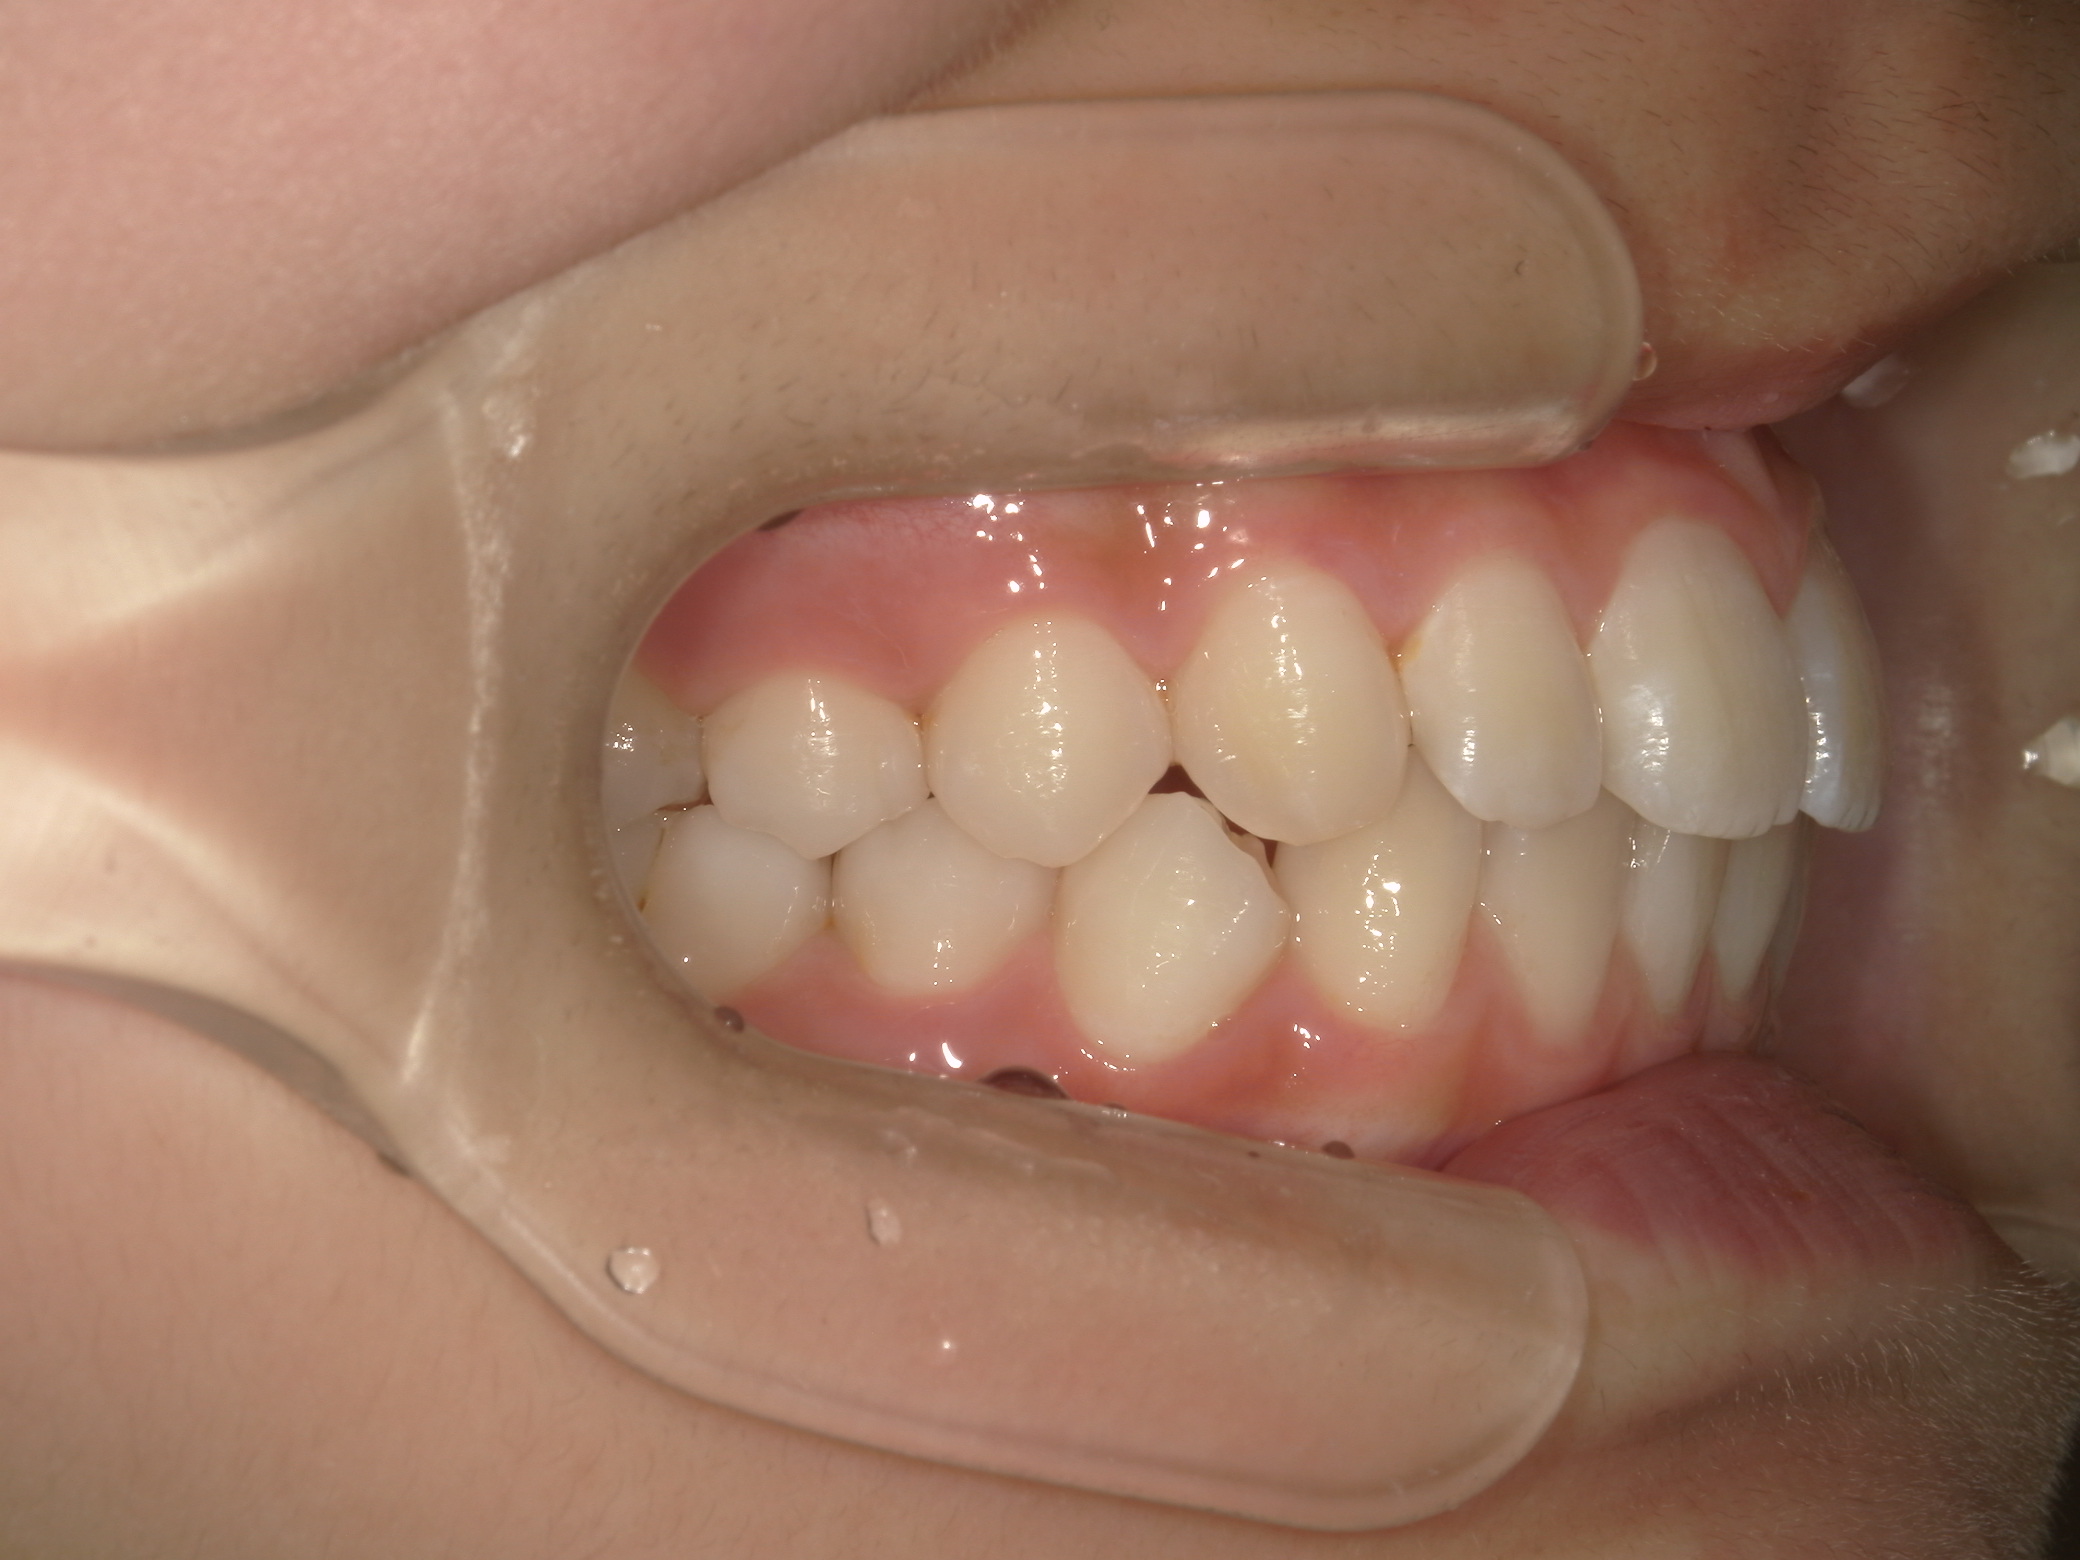

Before

After

舌癖が原因で、前歯が動揺していましたが、矯正治療を開始して動揺は収まりました。

矯正後、写真撮影時は 外傷で歯を打って動揺が出た時期だったため、 後ろから固定しています。

afterの写真は全て永久歯列になった時の写真です。